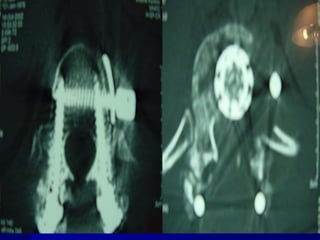

 AANN.. PPEERR..

 FF –– 2222 yyrrss

 FFaallll

 LLeevveell :: TT1122

 TTyyppee :: AA33..33

 AA..SS..II..AA.. :: EE

1st Posterior decompression

and stabilization

2nd anterior decompression